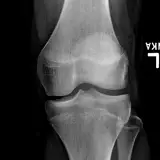

Over 2,100 interactive radiology cases, curated by radiologists for your level of training. Scroll, window, and view cases full screen — just like on PACS. Click linked findings in each writeup to jump straight to them on the image. Cases include sample reports, a focused discussion section, original illustrations, and videos.

Casos totalmente interactivos con las herramientas que esperaría de un PACS: scroll, ventana, zoom, pan, mediciones, ROI y modo de pantalla completa.

• Anotaciones enlazadas

Anotaciones extensas resaltan los hallazgos clave directamente sobre los casos. Haga clic en los hallazgos enlazados dentro de la descripción del caso para saltar a su ubicación exacta en el estudio.

Desplace, arrastre, ajuste ventana y amplíe como en una estación PACS de trabajo

Aprenda con eficiencia gracias a hallazgos de imagen anotados e ilustraciones